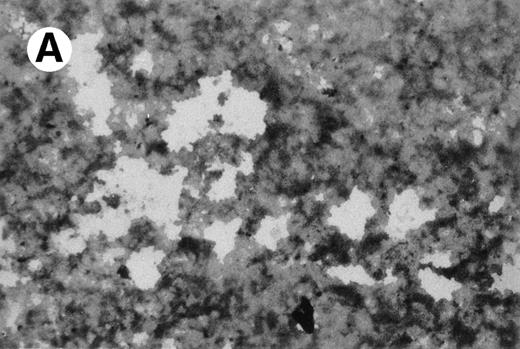

Specific staining showed that UG3 cells cultured with IL-3 were 98% positive for αNB esterase, 13% double-positive for αNB and NAC esterase (Fig 5A), and negative for peroxidase and NAP (data not shown). UG3 cells cultured with GM-CSF showed increased αNB activity and decreased NAC activity (Fig 5B) as compared with UG3 cells maintained in the presence of IL-3. A few of the cells cultured in the presence of GM-CSF were of macrophage-like appearance, having wide and irregular cytoplasm, and grew adherently. In contrast, about 45% of UG3 that were cultured in the presence of M-CSF grew adherently. Nonadherent cells obtained from M-CSF–supplemented culture showed the same morphological characteristics as UG3 cells that had been maintained in the presence of IL-3, but stained 100% positive for αNB and negative for NAC esterase (Fig 5C). Adherent cells obtained from cultures maintained in the presence of M-CSF showed macrophage-like morphology with widely spread cytoplasm containing vacuoles (Fig6A) and also displayed strong positivity for αNB esterase (Fig 6B). In contrast, UG3 cells cultured in the presence of G-CSF featured a slightly irregular cytoplasm, contained granules, and showed increase of NAC esterase positivity (Fig 5D). These cells were 4% positive for peroxidase (Fig 7A) and 6% for NAP (Fig7B). Some UG3 cells maintained in the presence of G-CSF had a segmented nucleus (Fig 7A).

Double staining for α-naphthyl butyrate esterase and naphthol AS-D chloracetate esterase of UG3 cells cultured with IL-3 (5 ng/mL; A), GM-CSF (1 ng/mL; B), M-CSF (100 ng/mL; C), and G-CSF (10 ng/mL; D) for 2 weeks. Original magnification, 200-fold. Histochemical analyses were performed using samples taken from four independent cell cultures.

CD68 expression was determined by immunohistochemistry of UG3 cells cultured with IL-3 (5 ng/mL; A), GM-CSF (1 ng/mL; B), or M-CSF (100 ng/mL; C) for 2 weeks. Original magnification, 200-fold. Histochemical analysis was performed with samples taken from three independent cultures.